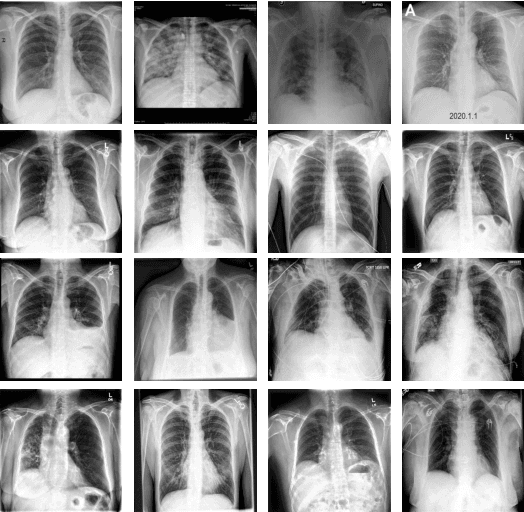

Abstract:The COVID-19 pandemic is causing a major outbreak in more than 150 countries around the world, having a severe impact on the health and life of many people globally. One of the crucial step in fighting COVID-19 is the ability to detect the infected patients early enough, and put them under special care. Detecting this disease from radiography and radiology images is perhaps one of the fastest way to diagnose the patients. Some of the early studies showed specific abnormalities in the chest radiograms of patients infected with COVID-19. Inspired by earlier works, we study the application of deep learning models to detect COVID-19 patients from their chest radiography images. We first prepare a dataset of 5,000 Chest X-rays from the publicly available datasets. Images exhibiting COVID-19 disease presence were identified by board-certified radiologist. Transfer learning on a subset of 2,000 radiograms was used to train four popular convolutional neural networks, including ResNet18, ResNet50, SqueezeNet, and DenseNet-121, to identify COVID-19 disease in the analyzed chest X-ray images. We evaluated these models on the remaining 3,000 images, and most of these networks achieved a sensitivity rate of 97\%($\pm$ 5\%), while having a specificity rate of around 90\%. While the achieved performance is very encouraging, further analysis is required on a larger set of COVID-19 images, to have a more reliable estimation of accuracy rates. Besides sensitivity and specificity rates, we also present the receiver operating characteristic (ROC), area under the curve (AUC), and confusion matrix of each model. The dataset, model implementations (in PyTorch), and evaluations, are all made publicly available for research community, here: https://github.com/shervinmin/DeepCovid.git